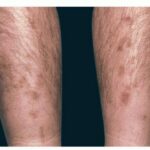

Diabetic dermopathy

Diabetic dermopathy , also known as shin spots, is considered the most common cutaneous finding in diabetes. According to one study, 40 percent of diabetic patients in an Israeli hospital had diabetic dermopathy, which was statistically significant in patients over the age of 50.Diabetic dermopathy appears as round to oval atrophic hyperpigmented lesions on the pretibial areas of the lower extremities. The lesions are usually bilateral and have an asymmetrical distribution. Histologically, lesions show edema of the papillary dermis, thickened superficial blood vessels, extravasation of erythrocytes, and a mild lymphocytic infiltrate. The extravasated erythrocytes leave hemosiderin deposits, which provide the brownish hyperpigmentation. The lesions of diabetic dermopathy resolve spontaneously, leaving scars behind